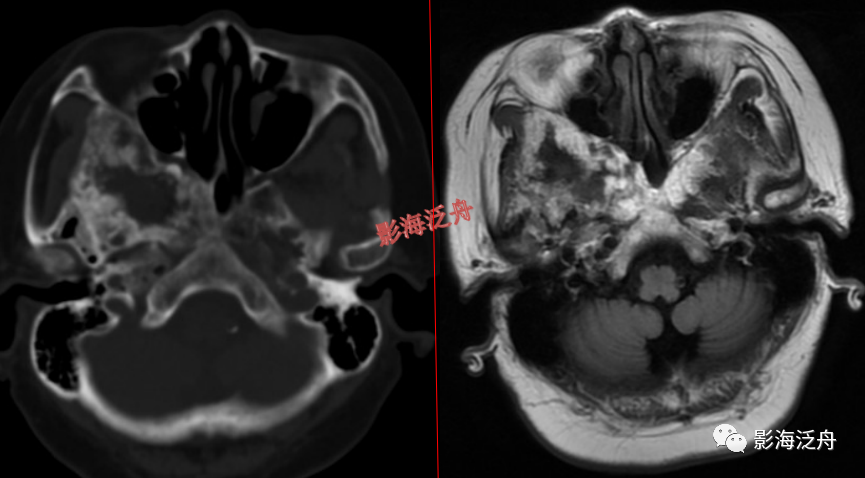

颅骨病变

左侧岩尖部囊性病变(红箭头),患者未术,病理不明。MR对骨质结构显示不佳,因此很多读者会忽略掉颅内骨质病变的观察,很多颅内病变,如三叉神经鞘瘤、鼻咽癌

等都会造成颞骨岩部(红色标注区)骨质破坏,因此,平时应对此处多加留意。黄箭头指听神经及内耳结构。

蝶骨骨纤维异常增殖症(红箭头),病灶内部可见特征性的囊变区(黄箭)。蝶骨的病变在MR上识别起来更为困难,因为蝶骨位于颅底部,此处骨骼、肌肉、脂肪等多种组织成分混杂,导致正常情况下也看起来非常乱。不要着急,慢慢学。

左侧顶骨骨纤维异常增殖症。病灶位于左侧顶骨板障区,局部骨质呈膨胀性改变,病灶边缘骨质硬化,呈明显低信号(红箭头),内部可见大片状絮状结构(黄箭)以及局灶性的玻璃样变性区(绿箭头)。